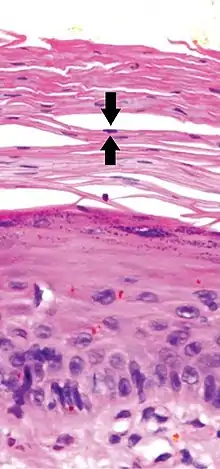

In contrast, hyperkeratosis (pictured) may also show a heterogeneous stratum corneum, but a preserved granular layer is seen.